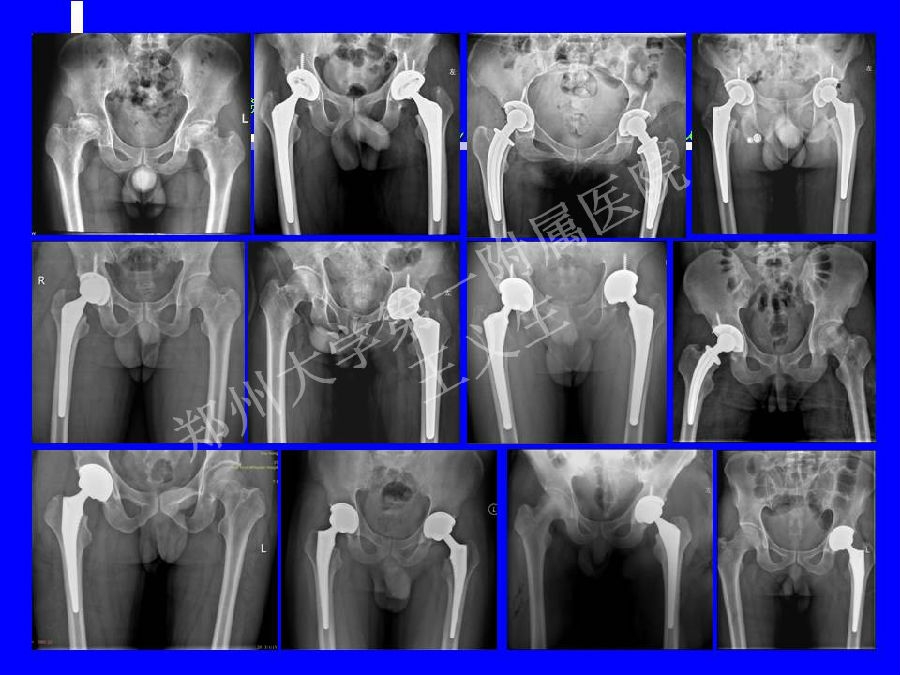

2014-04-24 文章来源:郑州大学第一附属医院骨科 王义生 我要说